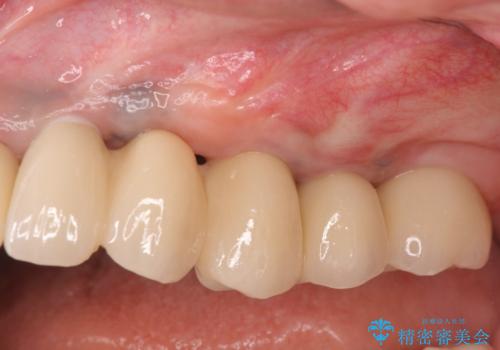

インプラント治療を行ったことでしっかりとした咬合関係を確立することができました。